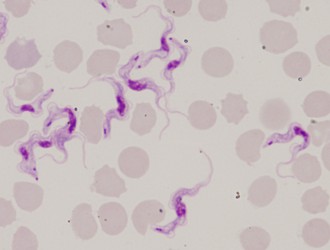

Kinetoplastids (Kinetoplastea) are a widespread and very important group of obligatory parasitic protists. At least one stage in the life cycle of all members of this group is represented by a slender and highly flexible cell equipped with one or two flagella, arising from a prominent flagellar pocket. Another hallmark is the presence of extensive mitochondrial DNA, termed kinetoplast DNA and trans-splicing. Usually a centrally located nucleus can be seen in Giemsa-stained smeared cells. The size of the kinetoplastid cell varies from about 10 to 100 microns in length, and never exceeds 20 microns in width. When present in the life cycle, the intracellular stage is usually round and lacks the flagellum.

Scientific Name | Trypanosoma brucei |

Identified By | Jan Votypka |

© 2008 Jan Votýpka